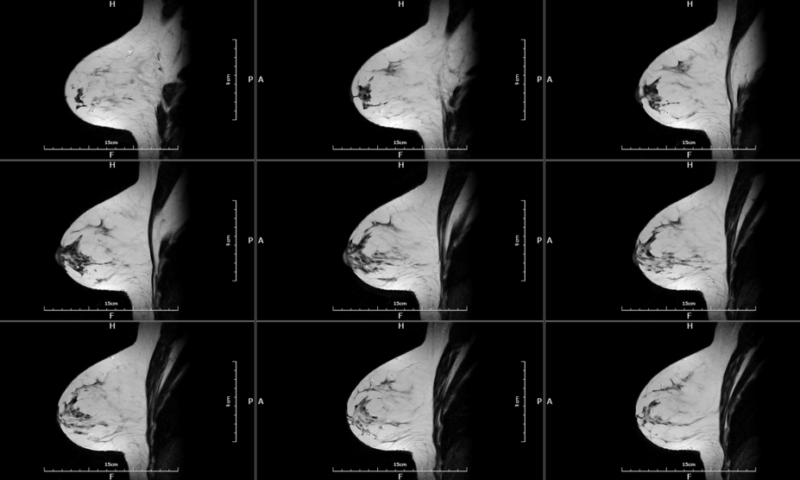

The EMMA 1.5T MRI is designed to offer breast imaging centers a new adjunctive tool to their current equipment options. Emma is a whole body MRI with dedicated breast coils for exclusive high-quality imaging.

In collaboration with leading breast cancer centers and following new published trends, the EMMA system extends MRI’s strong diagnostic utility with rapid and cost-effective – optimal breast MRI screening exams (AB-Breast MRI). It’s a cutting-edge, humanistic and affordable MRI Breast Scan.

Customized breast coils with 3 cup-size to deliver exceptional breast images.